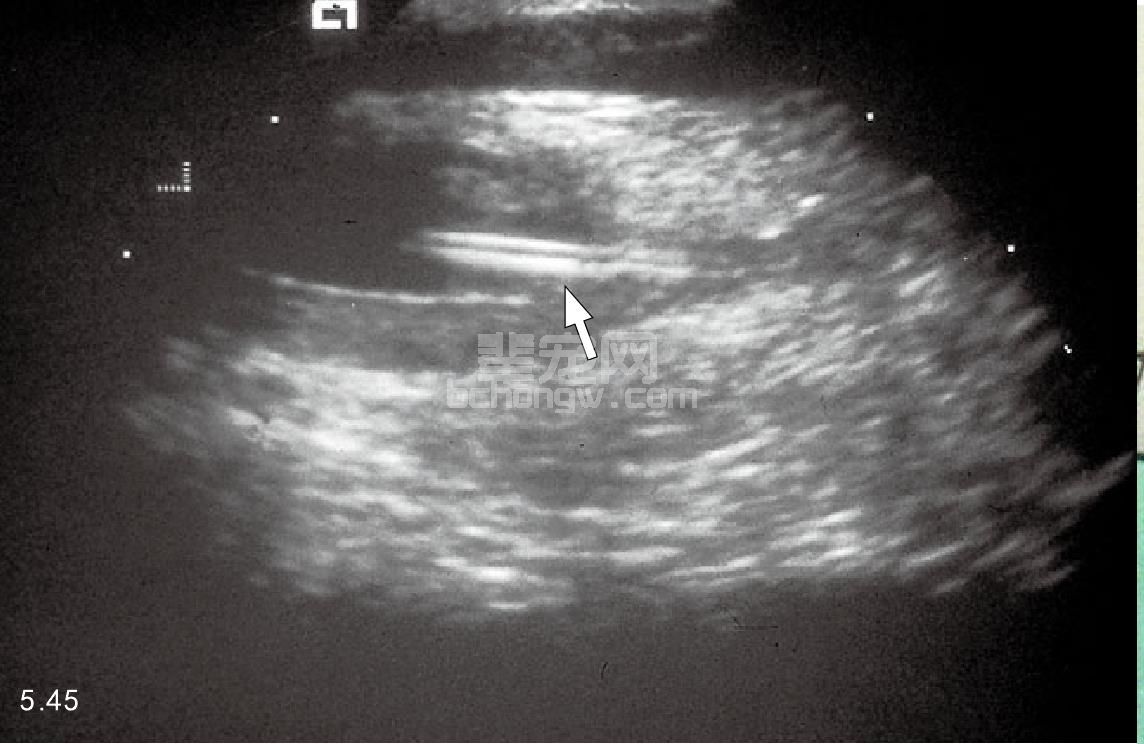

非阻塞性 通过尿液分析和尿液培养以及敏感性试验(对于可疑的很少发生细菌感染的病例)可以确定非阻塞性FLUTD。在尿液沉积物中,很大比例的猫会出现血尿,但是脓尿很少发生(图5.44)。没有出现血尿并不能排除是FLUTD,因为在尿液沉积物检查,正常的情况下用膀胱镜检查时也会见到损伤。尿液沉积物中晶体矿物质类型应引起注意。腹部的X线片检查显示在膀胱内有不透射线的尿结石,如草酸钙,但是双重膀胱造影或者超声检查,有时对检查一些透射线的结石和异物是有必要的(图5.45)。膀胱镜检查可以显示黏膜下水肿和点状的出血,称为团伞状出血,经常与突发性的FLUTD有关(图5.46)。

图5.45 超声检查猫的下泌尿道疾病,有一断裂的导尿管在膀胱内(箭头所指)。诊断前导尿管在消除阻塞后用了将近2年。